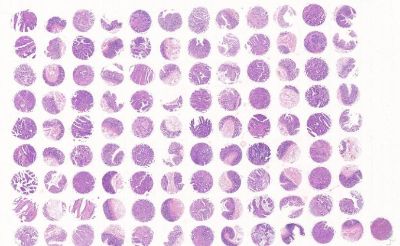

全片数字扫描服务

购买我公司芯片,可享受低价的IHC实验后芯片扫描服务;您的所有扫描数据将被安全地存储在云端服务器。您拥有专属密码,只要您需要,可以随时随地访问您所需要的数据,方便您的查看和保存。

芯片加工

中科光华 芯片加工

专业芯片设计师为您量身打造高质量芯片。1. 芯片内设对照;2. 组织齐全;3. 样本新鲜。